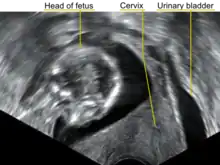

| A transvaginal ultrasound showing a retroverted uterus during pregnancy. The cervix lies posteriorly to the urinary bladder, and the uterus normally extends superiorly from it, but the direction of the body of the fetus reveals that the uterus extends backwards. | |